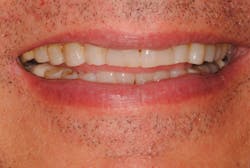

Due to the patient's excessive overjet, mandibular crowding, and a V-shaped maxillary arch form, we recommended orthodontic repositioning before completing the patient's restorative treatment. He elected to use Invisalign orthodontics. Treatment would align and procline the lower anterior teeth, bodily move teeth Nos. 8 and 9 lingually, and round out the maxillary arch. Orthodontic treatment was completed in 10 months. Next, we took a new set of diagnostic models and mounted them in CR.

The goal of restorative treatment was to establish centric holding stops on all of the patient's teeth in CR and establish a shallow anterior guidance in harmony with the envelope of function, which would disclude all of the posterior teeth in excursive movements. The patient's lower anterior occlusal plane was concave, so those teeth were built up in the wax-up. In addition, there was no tooth display at rest, so we lengthened the maxillary incisors by about 1.5 mm, improving the width-to-length ratio to 80%. (7)

Figure 5: After treatment

Figure 6: After treatment